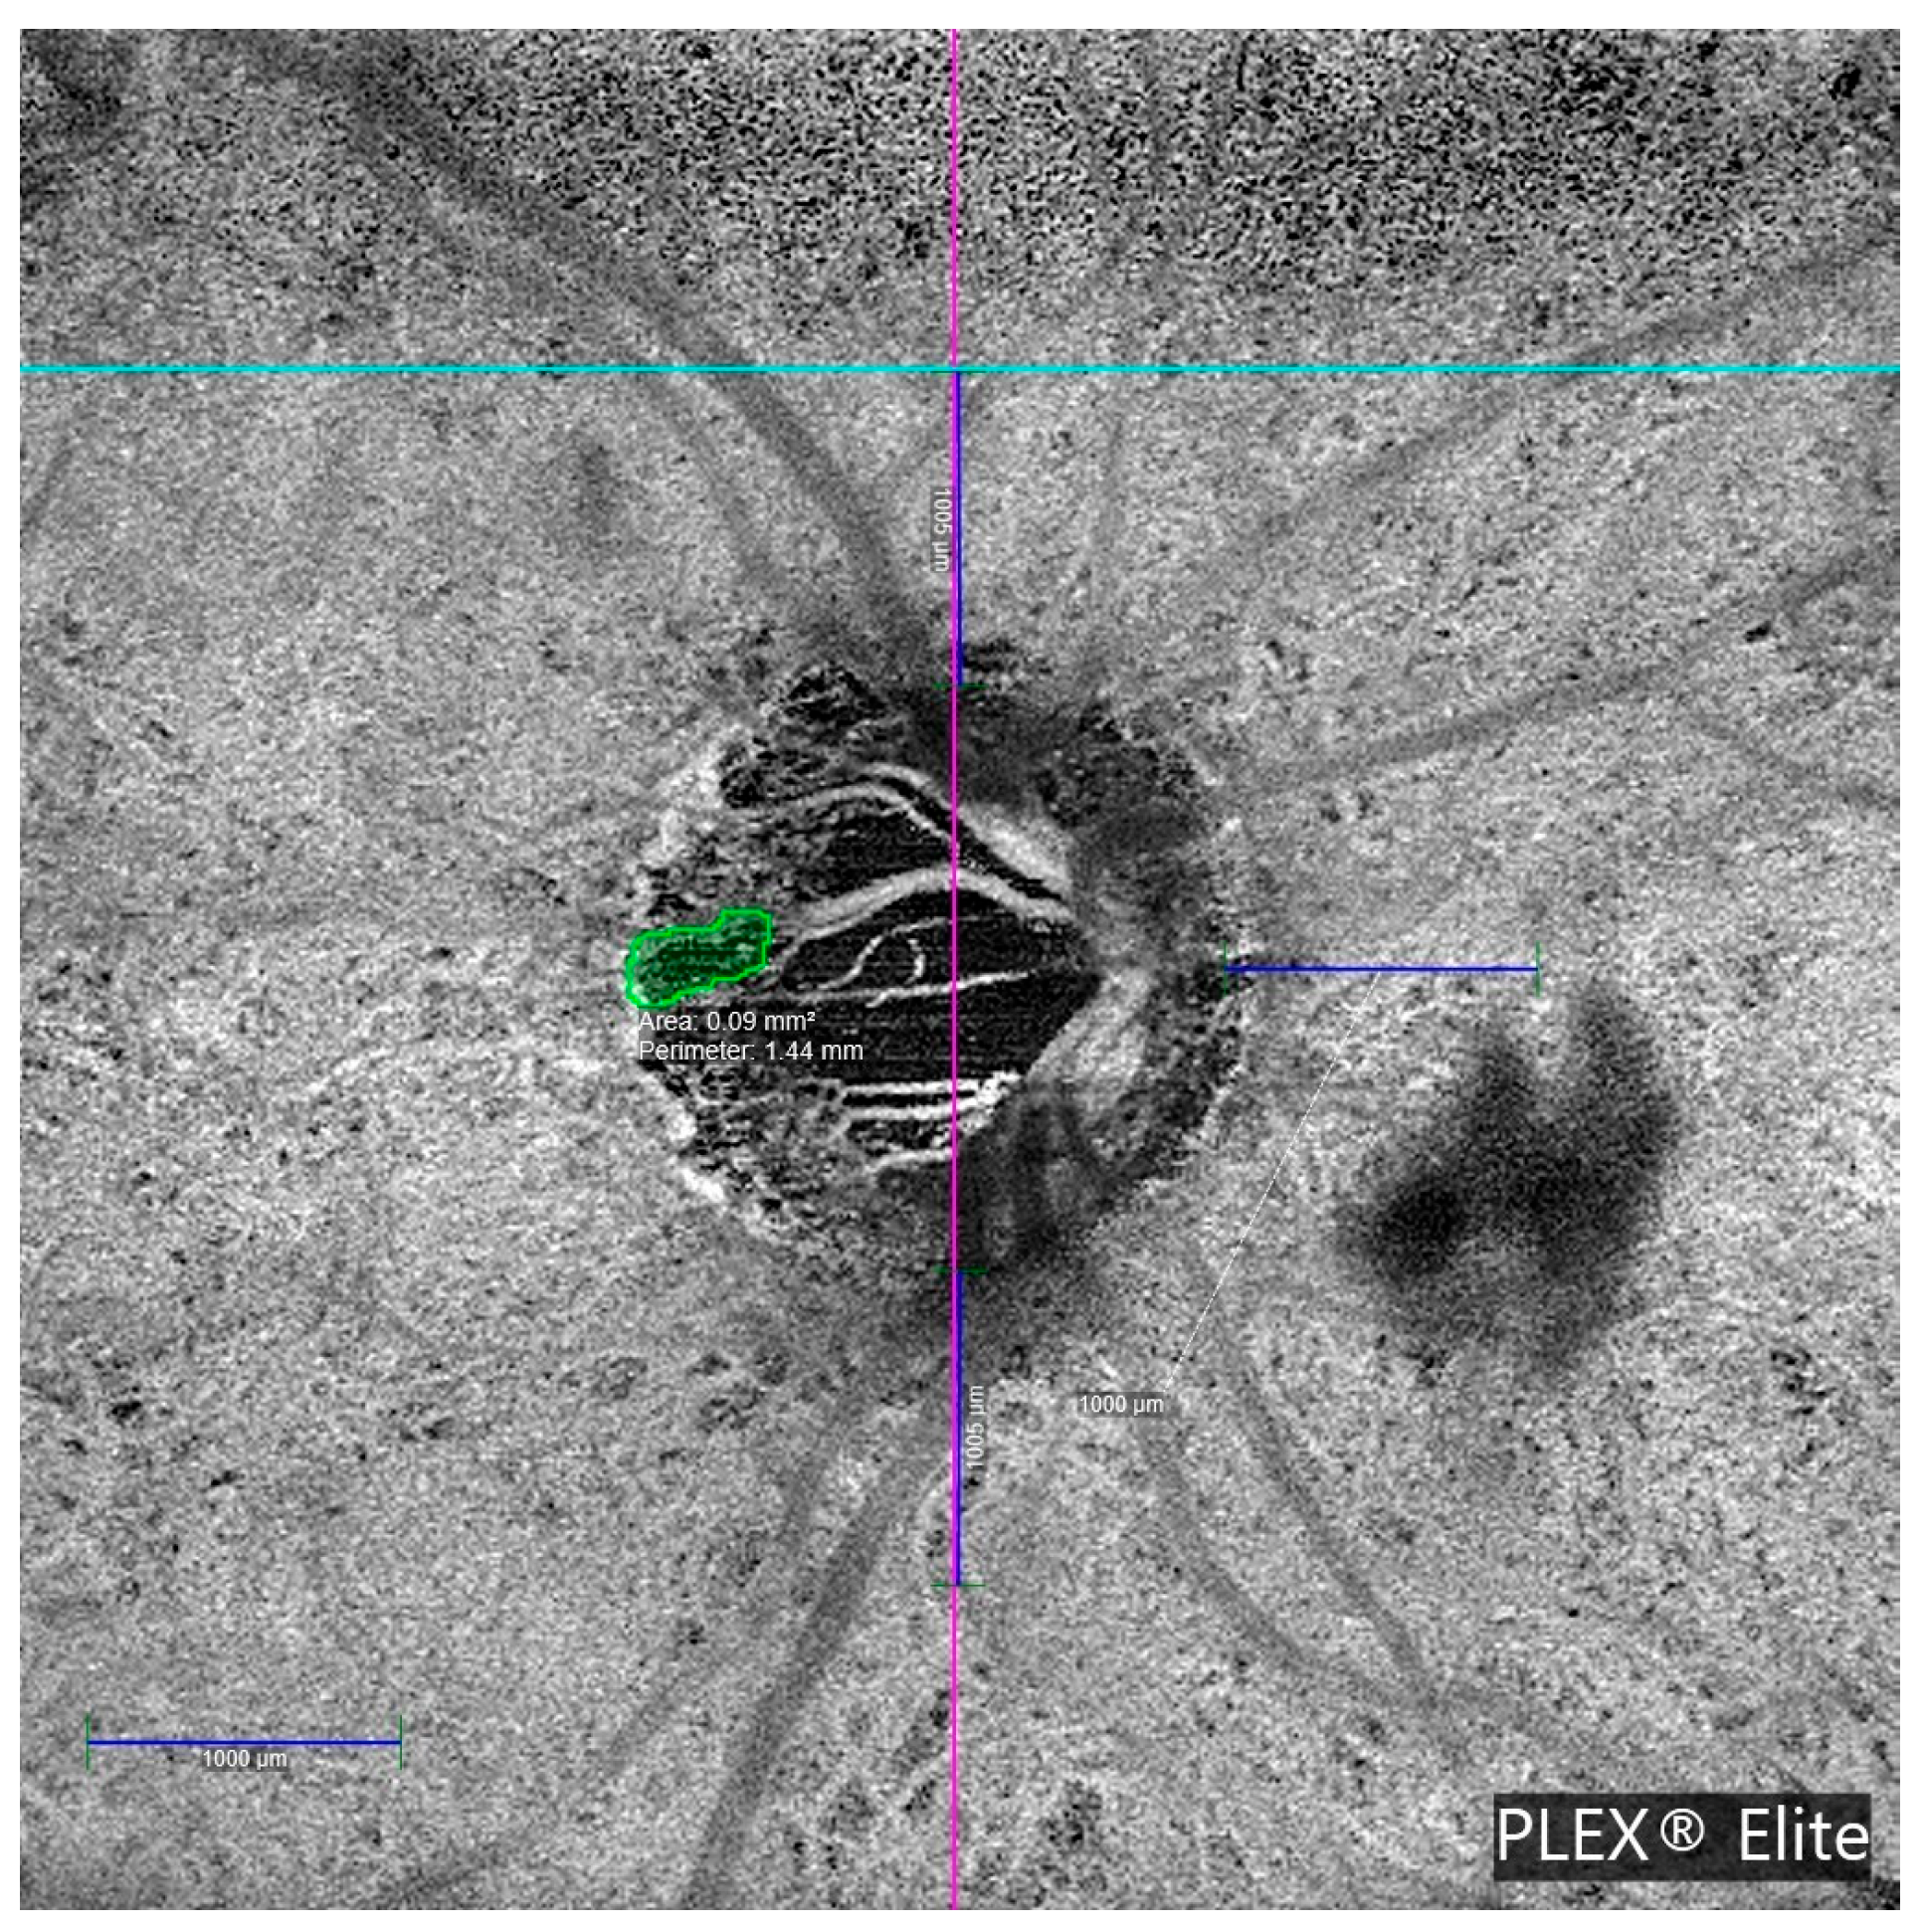

β-zone parapapillary (β-PPA) was identified and quantified in the OCTA images. β-PPA was defined as the area between the optic disc margin (inner border of the peripapillary scleral ring) and the RPE atrophy line, characterized by visible sclera and prominent choroidal vessels. Manual delineation of the disc margin and β-PPA was performed on en face OCTA images using B-scan references. Figure 3 illustrates this process.

Figure 3. Optical coherence tomography angiography (OCTA) en face image of the optic nerve head (ONH) acquired using the PLEX® Elite 9000 system. The image displays a manually delineated region of β-zone parapapillary atrophy (β-PPA), highlighted in green. The β-PPA area was calculated by subtracting the ONH area (2.33 mm2) from the total area (3.08 mm2). These parameters were used to assess structural alterations associated with microvascular dropout (MvD) in glaucomatous eyes.